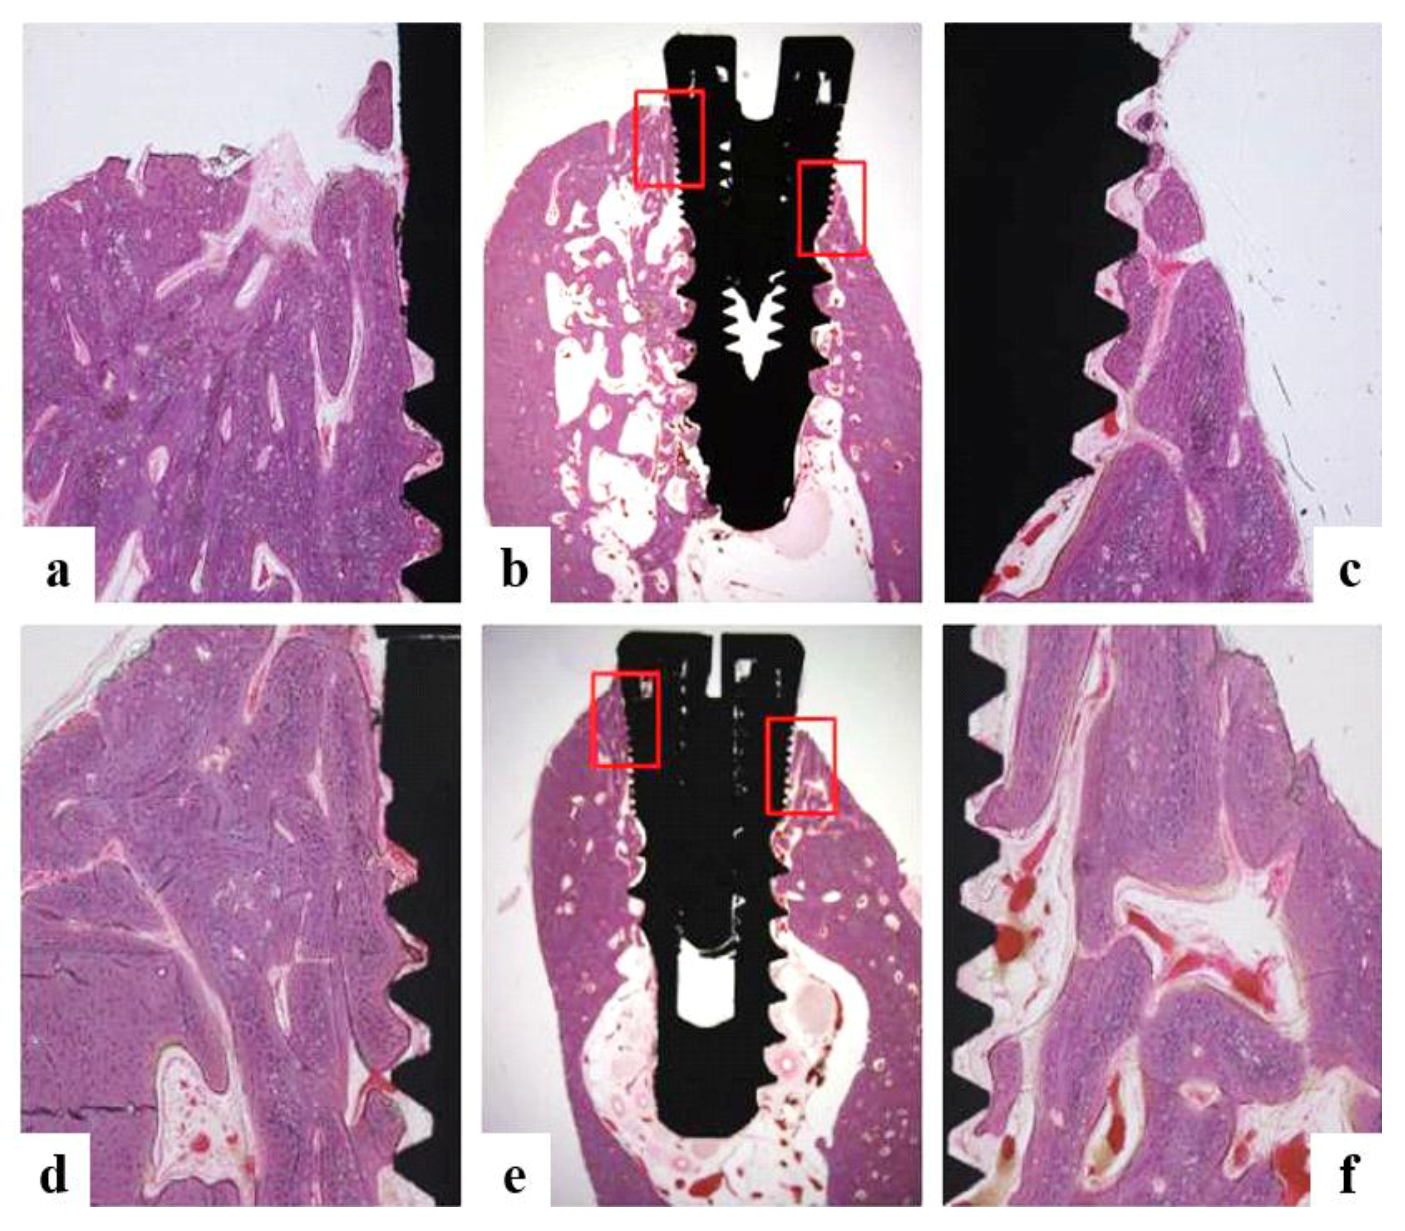

2.5.6. Histologic and Histometric Analysis

- Bone growth height in buccal defect areas (BG, mm): The thickness of bone that grew upward from the implant from the reference point on the buccal defect site on the alveolar ridge.

- Bone to implant contact in microthreads (microBIC, %): The bone to implant contact ratio was measured in buccal and lingual defect areas where the bone grew along the implant from the implantation reference point on the alveolar ridge.

- Bone to implant contact in macrothreads (macroBIC, %): The bone to implant contact ratio was measured in existing bone where the implant was implanted.

- Intra-thread bone density in macrothreads (ITBD, %): Intra-thread bone density was measured in the existing bone where the implant was placed.

3.4.4. Histomorphometric Analysis

| Group | BG (mm) | microBIC (%) | macroBIC (%) | ITBD (%) |

|---|---|---|---|---|

| Ti | 0.23 ± 0.22 a | 11.05 ± 5.09 a | 23.58 ± 1.63 a | 54.90 ± 7.24 a |

| Hepa/Ti | −0.06 ± 0.21 a | 9.27 ± 1.95 a | 18.47 ± 2.89 a | 53.98 ± 3.77 a |

| PDGF/Hepa/Ti | 0.12 ± 0.28 a | 9.59 ± 3.99 a | 20.62 ± 2.30 a | 61.64 ± 6.17 a |

| BMP/Hepa/Ti | 1.34 ± 0.17 b | 27.76 ± 3.03 b | 22.20 ± 2.89 a | 60.80 ± 3.32 a |

| PDGF/BMP/Hepa/Ti | 1.31 ± 0.12 b | 31.79 ± 3.90 b | 23.54 ± 2.30 a | 69.22 ± 3.96 a |

| * p | 0.000 | 0.000 | 0.544 | 0.244 |